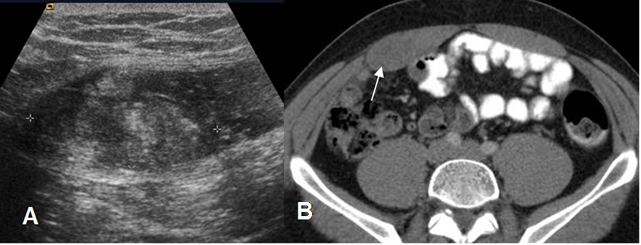

Fig 9. Hematoma muscular.

A: Ecografía. Lesión heterogénea localizada en el músculo recto anterior del abdomen, que corresponde a hematoma.

B: TAC axial. Engrosamiento muscular, con hematoma isodenso.